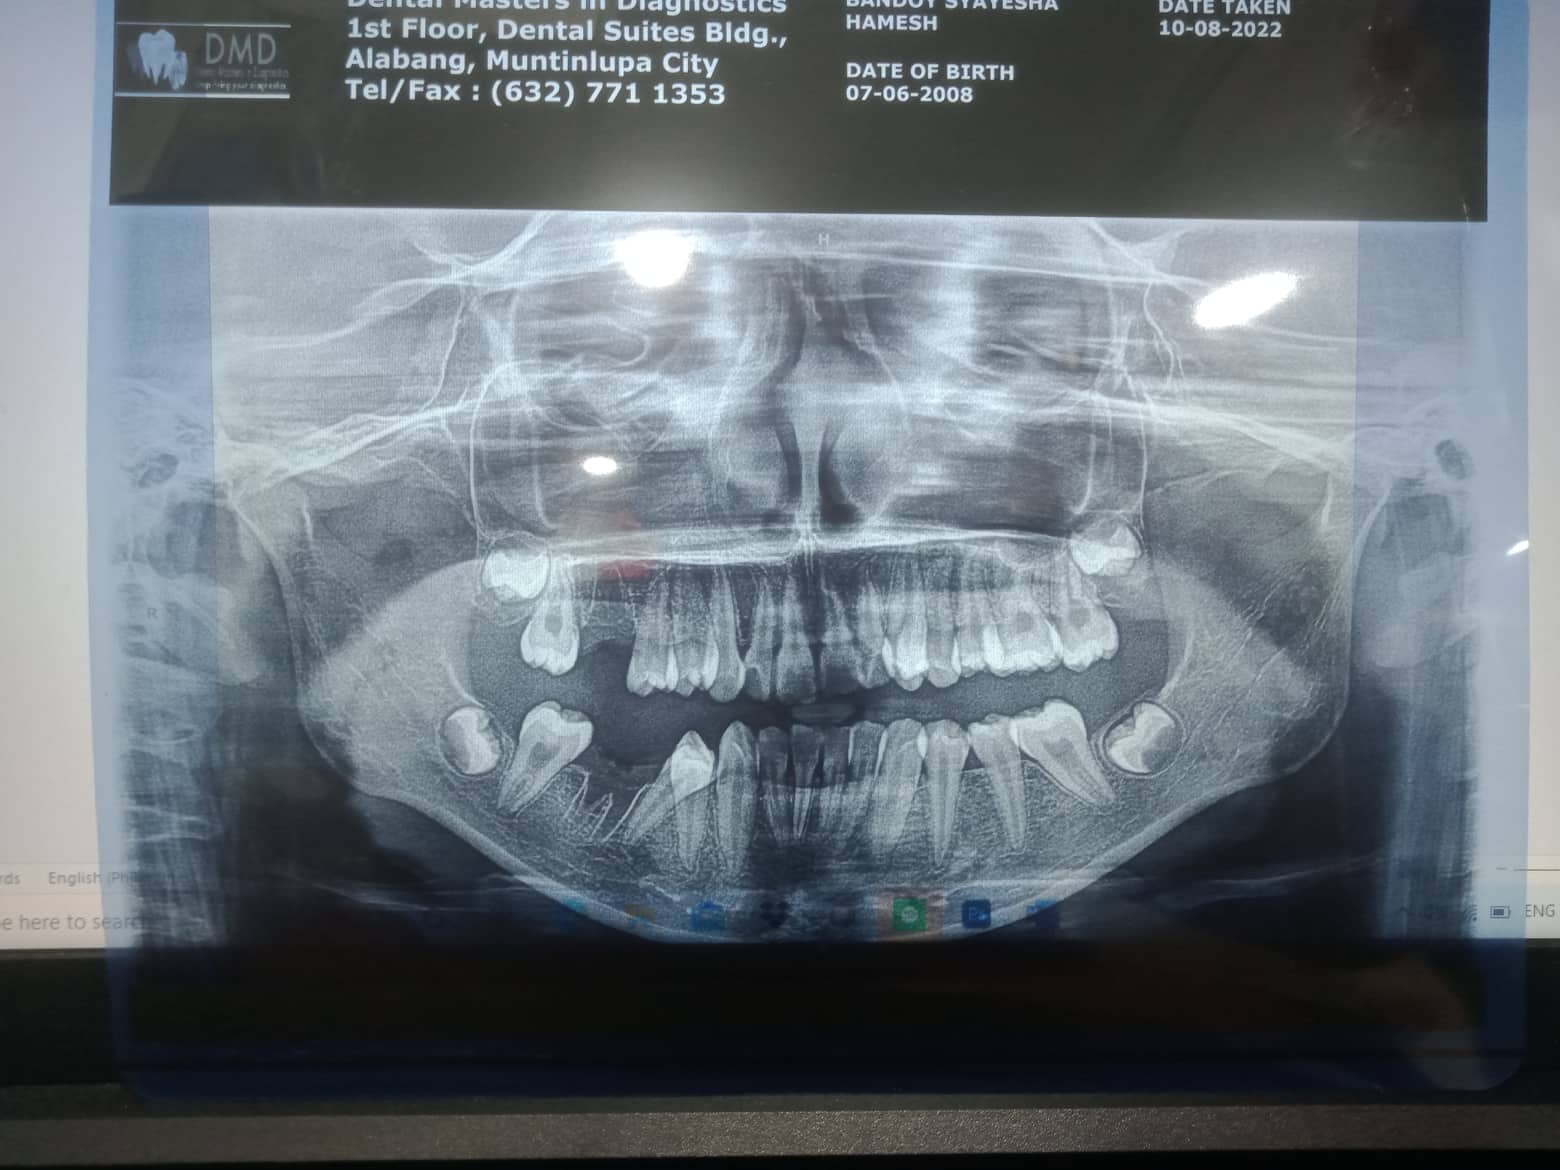

Edit Record Check our patient data records. Add patient information Patient Info Profile picture Last Name First Name Middle Name Birthdate Age Street Barangay City Country Zip Code Contact number Email Procedure 10/01/22 - OP(L), EXO #16, #46, GIVEN POST OP INSTRUCTIONS 10/08/22 - RESTO #11(LINGUAL/DISTAL), #22(MESIAL/LABIAL), MBT 0.22slot 14niti (upper), no brackets on lower *for extraoral photos 1/21/23- Upper Same wire, lower install brackets Install occlusial pads #47,#36 11/26/22--Lc 01/21/23-Upper-Same wire/L install bracket/ install occlusal pads #47,36 04/29/23- same wire UL/ Ligature wire #31,41 Resto #12L 06/30/23-Informed Consent Ortho Adjust UL- NiTi - 16 IPR #23D Coil spring b/w #14 08/26/23- 16 SS U 16 NiTi L *reattached #14 Fox 14 to 47 09/30/23- EXO 26 same wire 11/25/23- BT - New, 14 NiTi Lower #45 attached, 16 NiTi U same wire 02/03/24 16 NiTi lower 03/17/24 Adj. #14-15 chain #15-16 chain 18 SS upper 04/20/24 coil spring #23-24 coil spring # 13-14 class II elastic fox reattached #45 05/25/24 16 NITI L class II elastic rabbit 06/22/24 16x16 SS L 1 side class II rabbit 5oz. 08/24/24 same wire 09/21/24 Adj chain upper class II elastic rabbit 5oz ligature wire #11-#22 11/23/24 Reattached #45 same wire 01/25/25 Lost bracket #45 reattached #24,34 16 NITI L class II chipmunk 03/01/25 Reattached # 24,34,44 chain class II elastic rabbit 5oz 03/29/25 Adj reattached #24,34,44 elastic rabbit 5oz 04/26/25 adj reattached #34,44 kobayashi wire #12/22 class II elastic chipmunk 5oz 05/31/25 adj reattached #25,43.34,44 class II rabbit 3.5 oz crimpable hook (2) 06/28/25 Reattached #43,44 class II elastic rabbit 5oz 07/26/25 Reattached #43,35 lingual button #43,45 S elastic on QI and QIV classs II elastic rabbit 5 oz 08/16/25 Adj reattached #43,44 Elastic rabbit 3.5oz. 09/20/25 SAME WIRE ELASTIC RABBIT 5OZ REATTACHED #43,34 10/25/25 adj same wire reattached #33, 34 class II elastic - chipmunk 3.5oz elastic #44 to 14 11/29/25 adjustment File 310463486_1883567741974810_5783853081586165841_n.jpg File 2 310643315_413077354351399_6901125436255634455_n.jpg File 3 File 4 File 5 File 6 File 7 File 8 File 9 File 10 File 11 File 12 File 13 File 14 File 15 File 16 File 17 File 18 File 19 File 20 Retain Record Retain Record Yes No Save Your Changes